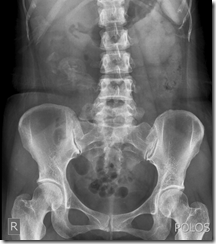

Pemeriksaan radiologi pada kasus pasien pelebaran ureter

Hasil Evaluasi pemeriksaan radiologi BNO – IVP :

BNO : Distribusi udara usus merata normal

Tak tampak batuopaq ditractus urinarius

1. Fungsi ren bilateral normal

2.Anatomi ren kiri normal,hydroneprosis grade 3 ren kanan

3.Kaliber ureter kiri normal,

Pelebaran ureter kanan sampai distal kemudian menyempit (stenosis)  di urterovesical Junction

4.Fungsi dan anatomi VU baik

polos

pemeriksaan radiologi BNO – IVP pada kasus ini sangat jelas terlihat pada ureter dextra, melebar, terlihat jelas pada fase post miksi.